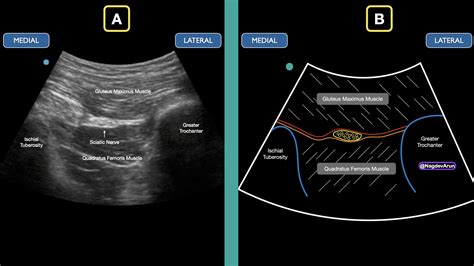

The success of the procedure relies heavily on precise placement. To ensure accuracy, modern medical practices utilize ultrasound guidance or nerve stimulation to visualize the nerve anatomy in real-time. This reduces the risk of nerve injury and ensures the medication is delivered precisely where it is needed.

Guidance Ultrasound or nerve stimulator identifies the precise location of the sciatic nerve.